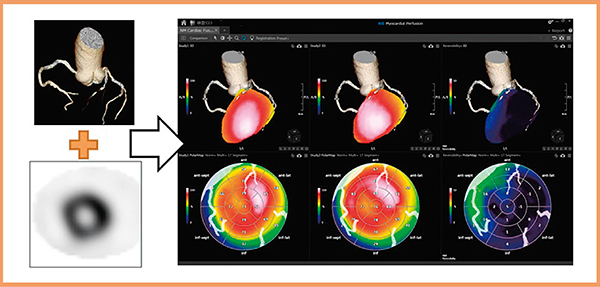

■冠動脈CT画像と心筋SPECTのフュージョン“NM Cardiac Fusion”

近年,ソフトウエアの進歩により,冠動脈の形態的評価を行う冠動脈CT画像と機能的評価を行う心筋血流SPECTをフュージョンさせる手法が開発されており,その融合画像は臨床の場で高く評価されている4),5)。

GCA-9300Rに搭載される“NM Cardiac Fusion”も画像フュージョン用アプリケーションの一つで,冠動脈CT画像とSPECT画像の3Dフュージョン表示が可能である。冠動脈の状態(走行・狭窄や石灰化の有無)と心筋血流の状態(虚血・梗塞の有無)を同時に観察することで,責任血管の判定・治療方針の決定・被検者への説明に効果が期待できる(図8)。

また,本アプリケーションではポーラーマップ解析画像も冠動脈CT画像とフュージョン可能で,被検者自身の冠動脈CT画像をオーバーレイ表示することで,複雑な血管走行をポーラーマップ解析画像上でも容易に把握できる。もちろん,ポーラーマップ解析はreversibilityやwashoutといった各種の解析に対応している。

図8 NM Cardiac Fusion使用画像

(データご提供:鹿児島大学様)